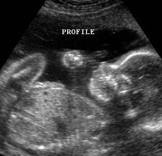

"Spontaneous expulsion of a human fetus during the first 12-20 weeks of gestation."

- The baby is now 14 weeks along. Doctors dilate the patients uterus to open cervix up. Once dilated, hours later. A tool is used to suck the baby out slowly, closing in its lungs and bashing its brains.

Manual Vacuum Aspiration

- Within the first 7 weeks of the pregnancy metal rods are put in place to stretch the cervix, wide enough so an anonymous doctor can get instruments in the uterus to suction the baby out.